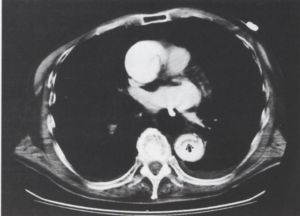

1. ábra.

A vese hilusok síkjában, az aorta falában lévő meszesedés megszakad - ez a ruptura helye, az aortától jobbra, ventralisan magas denzitású képlet, haematoma látszik. A jobb vese előtt a retroperitoneum beszűrt.

2. ábra.

Az 1. ábrával megegyező síkban, kontrasztanyag adása után készült felvétel, a kontrasztanyag egy része az aorta előtt látszik.